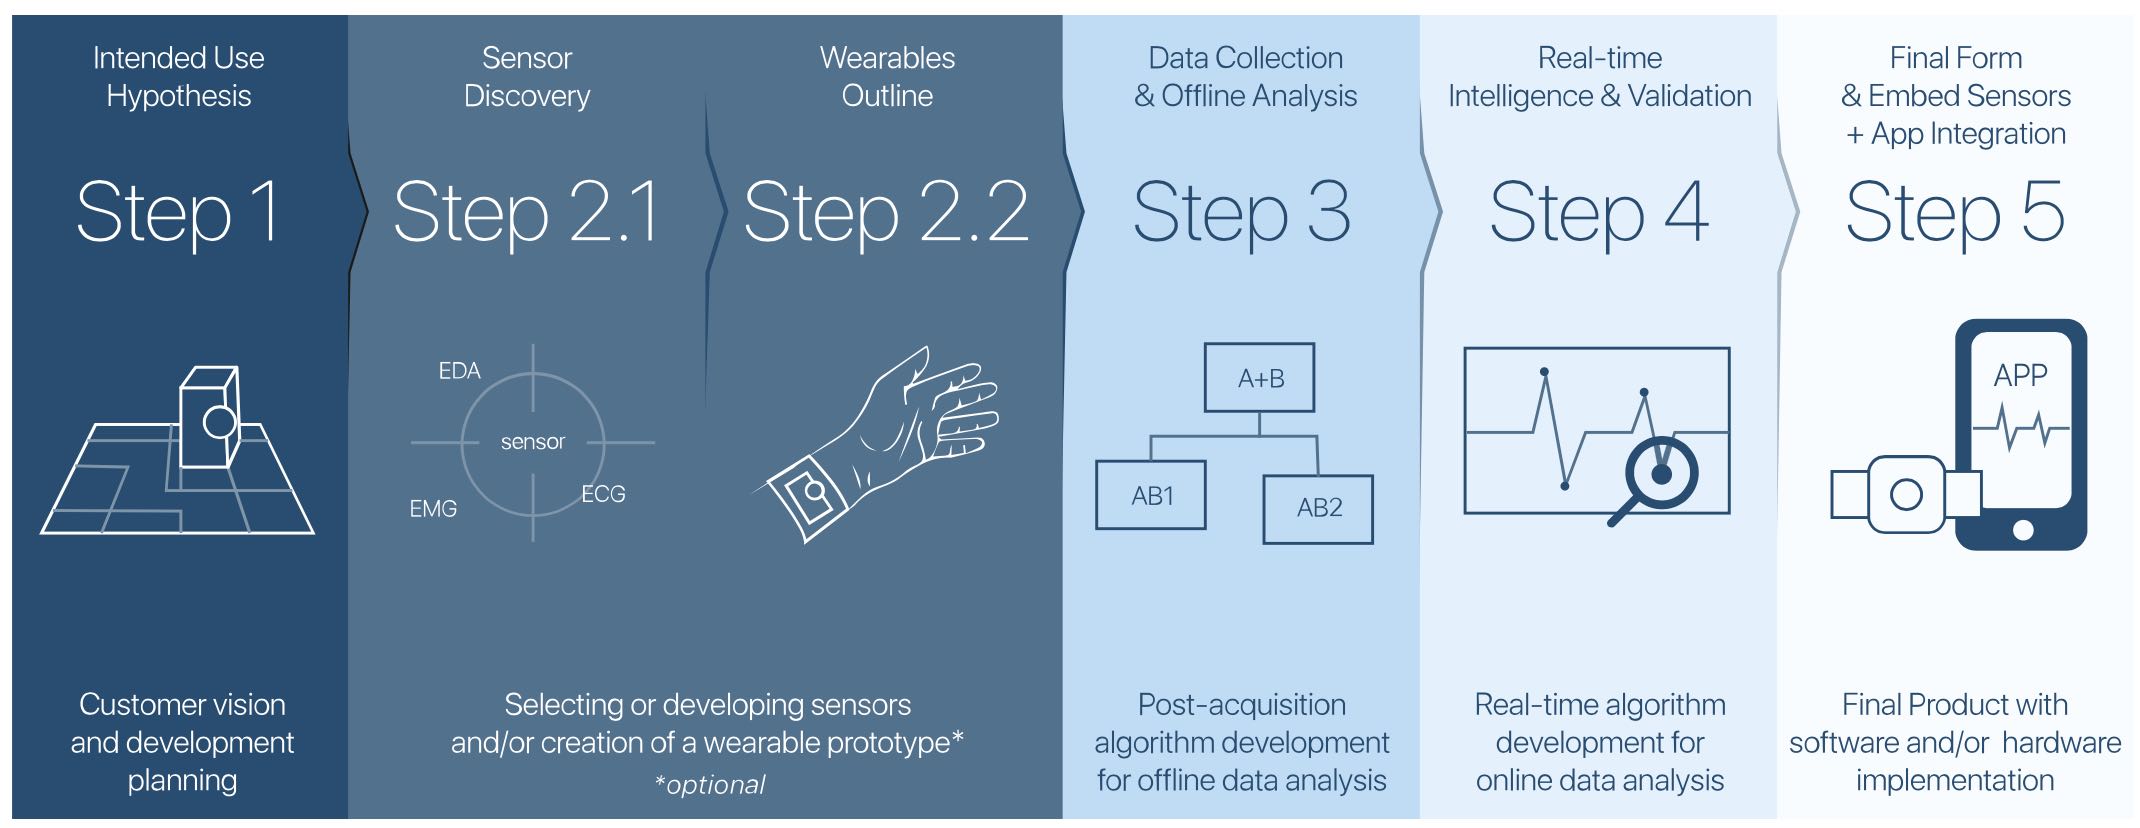

Founded in 2007, Arruda dos Vinhos startup PLUX has raised $1 million to develop biometric measurement systems and associated analytical algorithms. The company’s body sensors measure data like respiration, the electrical activity of the heart and skeletal muscles, and the movement and acceleration of body parts to aid physiotherapists and researchers in developing new medical solutions for patients.

Founded in 2007, Arruda dos Vinhos startup PLUX has raised $1 million to develop biometric measurement systems and associated analytical algorithms. The company’s body sensors measure data like respiration, the electrical activity of the heart and skeletal muscles, and the movement and acceleration of body parts to aid physiotherapists and researchers in developing new medical solutions for patients.

PLUX’s sensor packs come with software that visualizes and analyzes these biosignals, or you can opt for custom sensor and algorithm development for specific R&D projects. Global clients include the likes of Intel and Vodafone with whom PLUX has developed wearables for patient monitoring, therapy management, and hands-free control of devices.